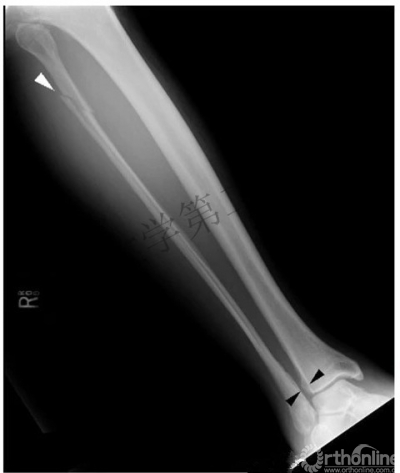

瑞麟导读:Maisonneuve骨折是踝关节骨折中一种特殊的类型,分型中属于LH旋前外旋III度及旋前外旋IV度、Weber分型中的C型骨折。

因其存在腓骨高位的骨折,比较容易漏诊,在查看患者时要特别注意小腿近端的疼痛及压痛,X片检查时尽量拍摄胫腓骨全长片。

1. 骨间膜损伤及腓骨高位骨折

2. 踝关节内侧结构损伤(内踝骨折或三角韧带损伤)

3. 下胫腓前韧带损伤

五、Maisonneuve骨折的诊断

2. 对于踝关节损伤的患者应注意对腓骨近端的查体,并行胫腓骨全长X线片。